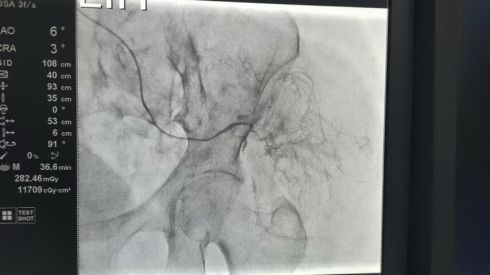

Основные способы лечения – это хирургическое удаление и химиотерапия. Объем удаления опухоли зависит от того, какая стадия заболевания диагностирована. Если опухоль небольшая, эндоскопическим методом (через нос) удаляют пораженный кусочек желудка. На поздних стадиях приходится полностью удалять желудок, соединяя пищевод с тонким кишечником.